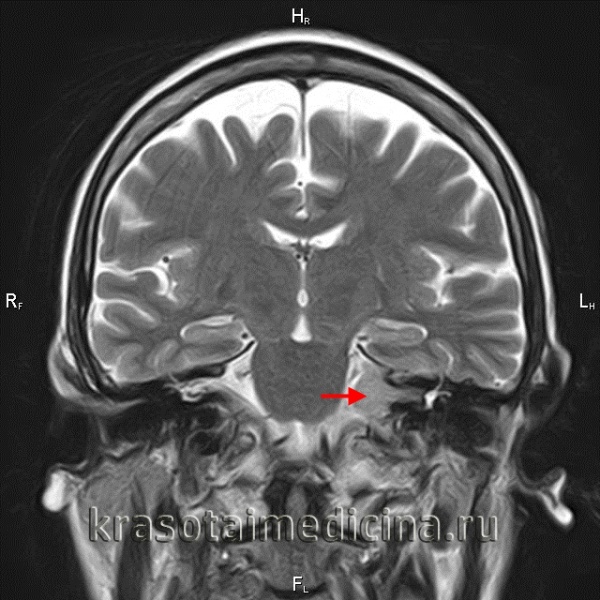

Оптимальными способами визуальной диагностики являются компьютерная томография (КТ) и магнитно-резонансная томография (МРТ) головного мозга. Эти исследования принято проводить с контрастным усилением, так как оно позволяет обнаружить даже небольшие новообразования [14] . Иногда опухоль обнаруживается случайно — при проведении КТ или МРТ головного мозга по другому поводу [13] . По результатам этих исследований можно поставить точный диагноз, выявить локализацию опухоли, её размеры, структуру, отношение к окружающим тканям задней черепной ямки, спланировать тактику хирургического или радиологического лечения [12] .

Более точно установить диагноз «невринома слухового нерва» помогает рентгенография и методы нейровизуализации. На ранних стадиях при малых размерах невриномы (до 1 см) она, как правило, не визуализируется при помощи КТ головного мозга. Поэтому проводят рентгенографию черепа с прицельным снимком височной кости. В подтверждение диагноза вестибулярной шванномы свидетельствует расширение внутреннего слухового прохода. Поскольку невриномы хорошо поглощают контраст, возможно использование КТ с контрастированием. При этом визуализируется образование с четкими гладкими контурами.

МРТ головного мозга в случае невриномы выявляет на Т1-взвешенных снимках гипо- или изоинтенсивное, а на Т2-взвешенных - гиперинтенсивное образование. Для опухолей размером 3 и более см характерна гетерогенность сигнала, связанная с наличием в них кистозных участков. Возможна визуализация деформации ствола мозга и мозжечка. При проведении контрастной МР-томографии в 70% наблюдается гетерогенное накопление контраста.